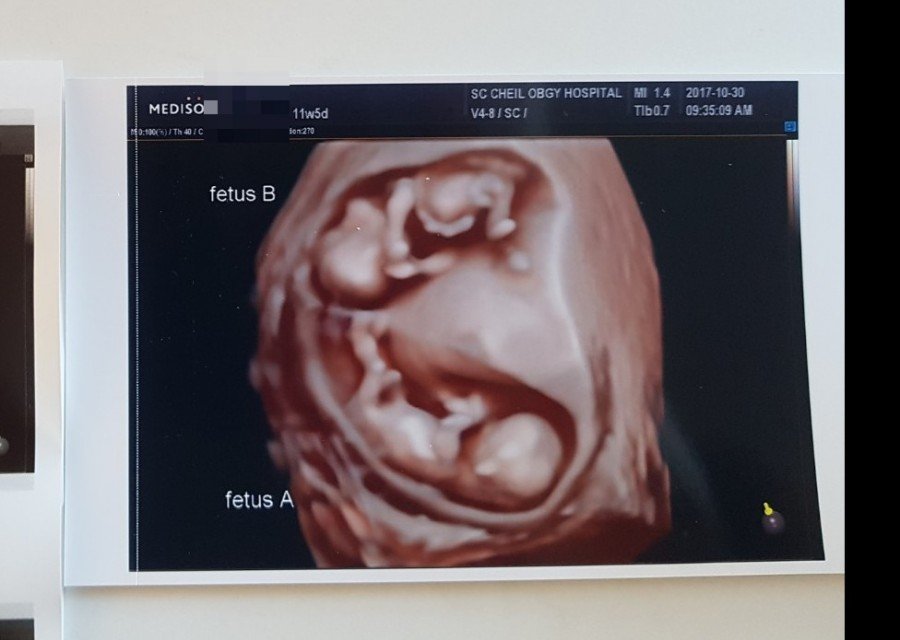

얼렁뚱땅 투샷

11주 5일쯤의 얼렁뚱땅_

A가 일렁이, B가 뚱땅이.

젤리곰에서 이제 정말 사람형태를

갖추었구나. 기특해 아가들.